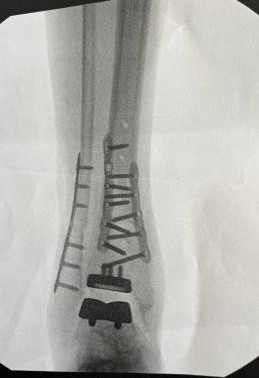

After too many running miles on an ankle that was broken as a child, every step was painful! I tried all sorts of procedures to eliminate the constant pain with no luck (injections, PRP, wrapping/braces, inserts, medication). I finally decided surgery was the best option. I met with a few orthopedic surgeons and their responses were varied (fusion, ankle realignment, and ankle replacement). I decided to make an appointment with Dr. Cody at HSS Stamford. She was very helpful and explained all the options and said she could do the realignment and replacement in the same surgery. That worked! I had the surgery early February and it took a few months of recovery with crutches, boot, and PT. Now no pain! I am amazed how good my ankle feels and I'm walking normally pain-free! The true test was recently when I went to Rwanda to see the gorillas and after seven months since surgery I was able to climb the mountain up to the jungle where the gorillas were living! I could not have done that last year! Dr. Cody is a truly gifted surgeon and is able to create miracles. I know firsthand! Thank you!